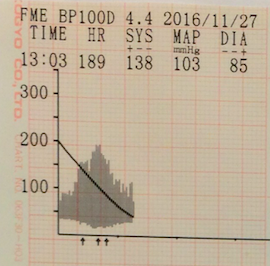

④血圧測定

高血圧になっていないかどうかを確認します。

正常な血圧(オシロメトリック法)